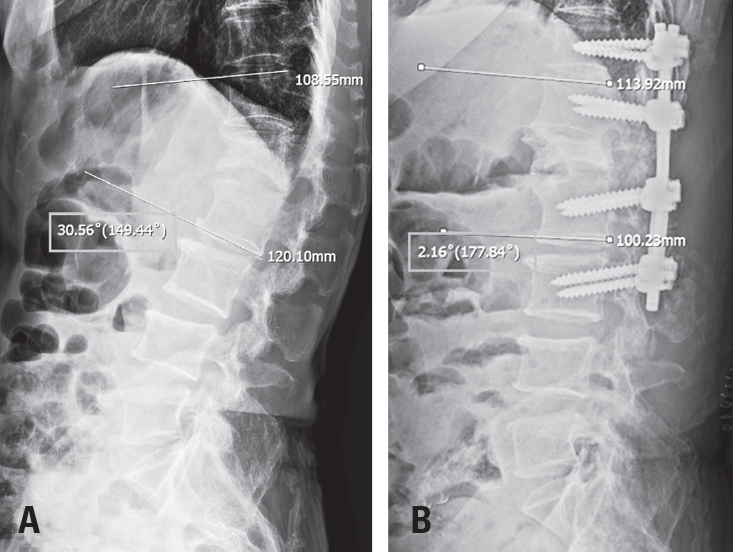

Spine-Shortening Osteotomy for Recurrent Adult Tethered Cord Syndrome Exacerbated by Traumatic Kyphosis: A Case Report

Tethered cord syndrome (TCS) is a condition in which the spinal cord becomes pathologically stretched due to various congenital or acquired etiologies, leading to progressive neurological symptoms. While surgical detethering is the gold standard for pediatric patients, adult-onset recurrent TCS presents a significant surgical challenge. Reoperation carries substantial risks—including spinal cord injury, cerebrospinal fluid leakage, and a high rate of retethering—often resulting in suboptimal long-term outcomes. Recently, spine-shortening osteotomy (SSO) has emerged as an alternative technique to reduce spinal cord tension without direct manipulation of the neural elements. Here, we report a case of recurrent adult TCS associated with a lipomyelomeningocele, which was exacerbated by post-traumatic kyphosis from an L1 compression fracture. The patient was successfully treated with SSO at the L1 level. This case highlights the utility of SSO as a safe and effective alternative to conventional revision detethering, particularly in complex cases involving spinal deformity.